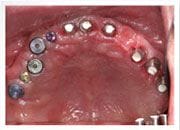

植牙過程

植入植體